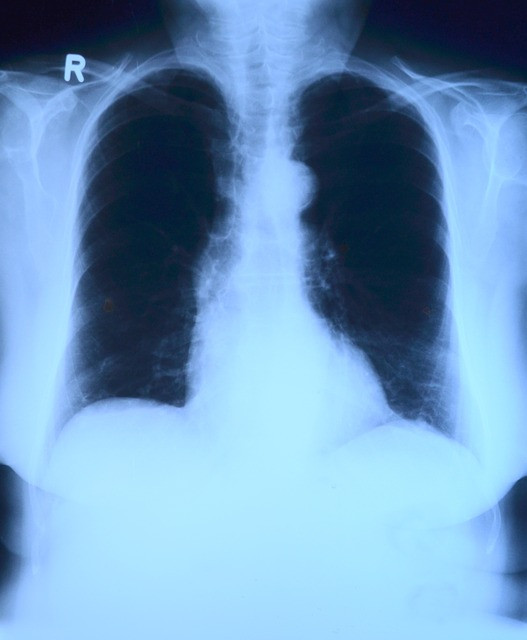

X-thorax bij verdenking pneumonie

Nieuw onderzoek toont aan dat huisartsen die een patiënt verdenken van een pneumonie hierin vaak worden bevestigd met een röntgenfoto. Hoe sterker de huisarts een longontsteking vermoedt, hoe vaker er een pneumonie wordt aangetroffen.